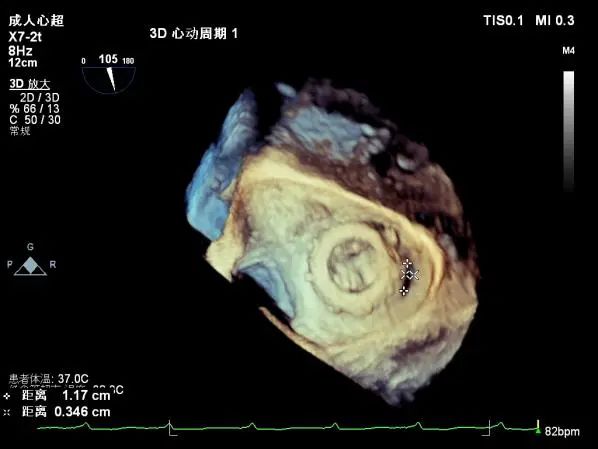

心脏超声示:二尖瓣位生物瓣置换术后 考虑生物瓣中-重度狭窄、中度瓣周漏及轻度反流;三尖瓣位生物瓣置换术后 生物瓣钙化、中度瓣周漏及轻度反流;右房内所见异常回声,考虑附壁血栓可能;心脏扩大(左房+右房) 肺动脉高压可能;主动脉硬化并瓣膜轻度反流;主肺动脉扩张并肺动脉瓣轻度反流;左室收缩功能正常,右室收缩功能指数明显降低。

升主动脉管壁回声增强;主肺动脉增宽。二尖瓣位生物瓣瓣架固定,瓣叶增厚、回声增强,局部粘连,致瓣叶开放受限(PHT法测有效瓣口面积约0.9-1.1cm²)、关闭欠佳,瓣叶与内侧瓣架见探及缝隙约3-4mm。三尖瓣位生物瓣瓣架固定,瓣尖增厚、回声增强,稀叶启闭尚可,瓣叶与内侧、外侧瓣架分别探及缝隙约3mm、1mm。主动脉瓣关闭欠佳:余瓣膜形态、结构未见明显异常。

二尖瓣位生物瓣舒张期峰值流速加快,平均跨瓣压差约9-11mmHg,探及瓣周漏(主要源于内侧瓣架)及瓣中反流。三尖瓣位生物瓣舒张期峰值流速大致正常(约1.52m/s),探及瓣周漏(主要源于内侧瓣架)及瓣中反流。探及主动脉瓣及肺动脉瓣反流束。估测PASP约46mmHg(可能低估)。

术前食道超声示:

术前食道超声